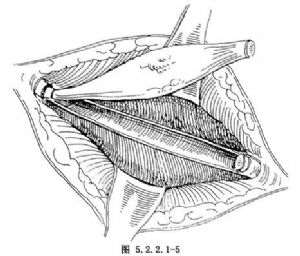

(3)切除腫瘤:多數良性腫瘤僅切除腫瘤組織或腫瘤侵犯的肋骨即可(圖5.2.2.1-5)。